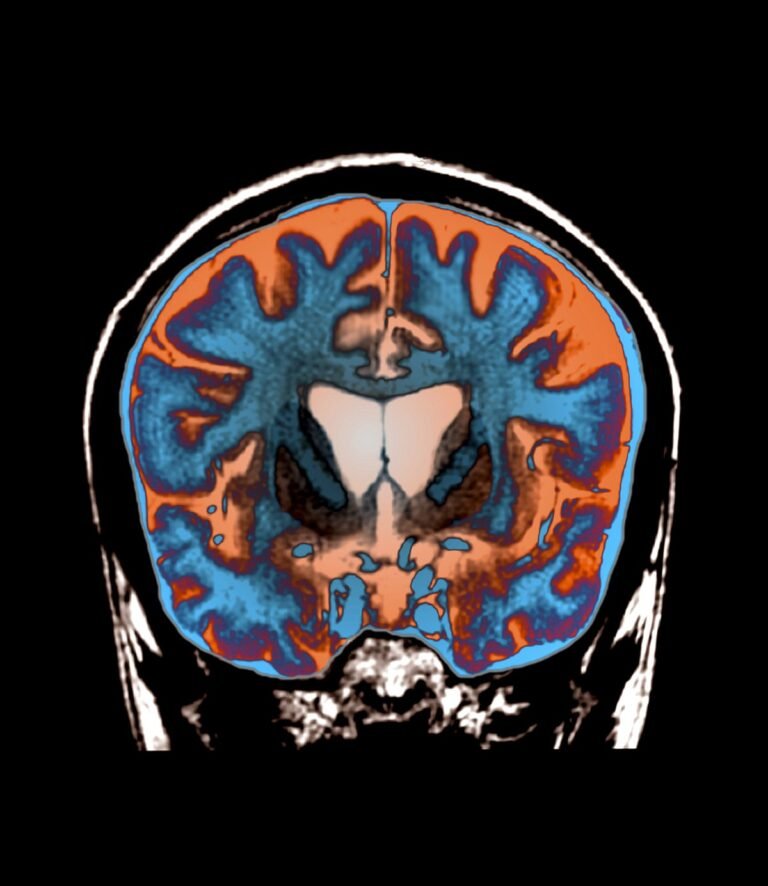

In some ways, Huntington’s disease seems like it should be the easiest neurodegenerative condition to treat. Unlike Parkinson’s and Alzheimer’s, scientists know exactly what causes Huntington’s: a mutation of the HTT gene in which a short, three-letter DNA sequence is repeated many times, causing it to produce a faulty version of the huntingtin protein. These faulty proteins accumulate in a deep brain structure called the striatum and cause symptoms such as uncontrollable movements, muscle spasms and cognitive decline that worsen over time.

Unlike ASOs, the new gene therapy drug AMT-130 is a one-time treatment, but it also involves lengthy and invasive brain surgery. Physicians insert catheters into deep parts of the brain where they can deliver the AMT-130 drug right to the neurons in the striatum that produce the abnormal huntingtin protein. The medication is transported through “shuttles” called adeno-associated viruses—noninfectious viral shells that can be packaged with genetic material. This genetic payload enters neurons, where it continuously produces tiny pieces of genetic code called microRNA. These microRNA specifically target and degrade messenger RNA carrying the instructions to build more huntingtin protein, therefore lowering the amount of huntingtin protein in the cell.